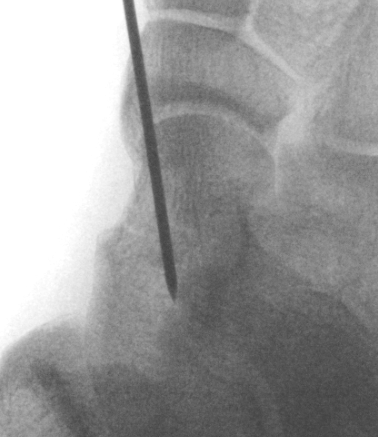

Canale view

- evaluates talar neck

- foot everted 15 deg

- look for medial shortening / varus

Cannulated screws

Xrays

| AP | Lateral | Canale View |

|---|---|---|

| Entry point of the screws |

Evaluate neck reduction

|

Evaluates the neck reduction |

Lateral off articular surface Medial through articular cartilage |

Depth of screws |

Beam angled 75o to foot Foot 15o pronated |

AP, Canale and Lateral xray